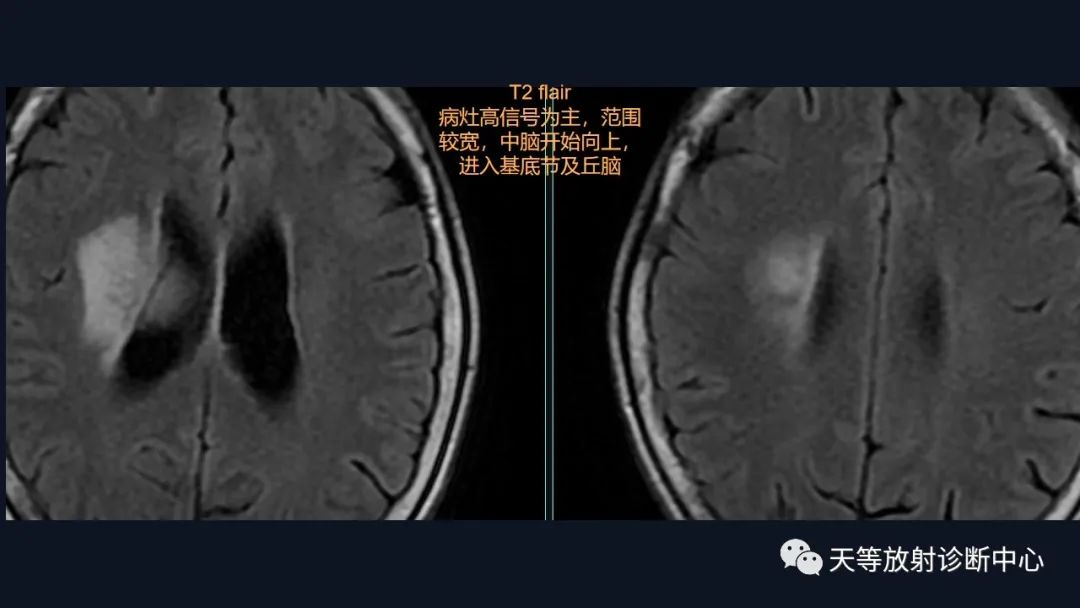

本病例影像学特点:

脑内占位的特点:

1、刀切征

2、凹陷征或肚脐凹征

3、尖角征

4、多发

5、DWI呈稍高信号

6、形态上怪异

6、NAA及Cho减低,出现导致LL峰。

结合颈部、胸廓入口区及腋窝多发淋巴结肿大并相互融合。

综合考虑淋巴瘤